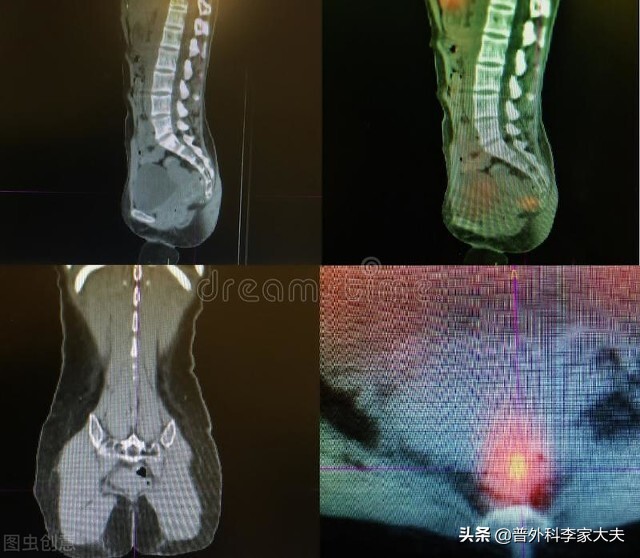

解决直肠癌Ⅱ期患者术后复发的第一个难题是,术前尽可能完善检查,通过外科专家与影像专家的共同努力,甚至借助于远程影像医疗的加持,来减少肠癌病理分期的错误风险。

直肠癌

有条件的患者,还可以到影像诊断水平高,尤其是肿瘤多学科会诊做得好的医院,进行肠癌疾病的诊治。当然,如果能找到一位诊治水平高、考虑问题全面,病情观察细致到位,并且不容易出医疗并发症的外科专家,却更是上上之策。只要患者的术前的精准评估到位,加上术中规范的手术治疗,相信会大大减少直肠癌Ⅱ期患者术后复发的风险。